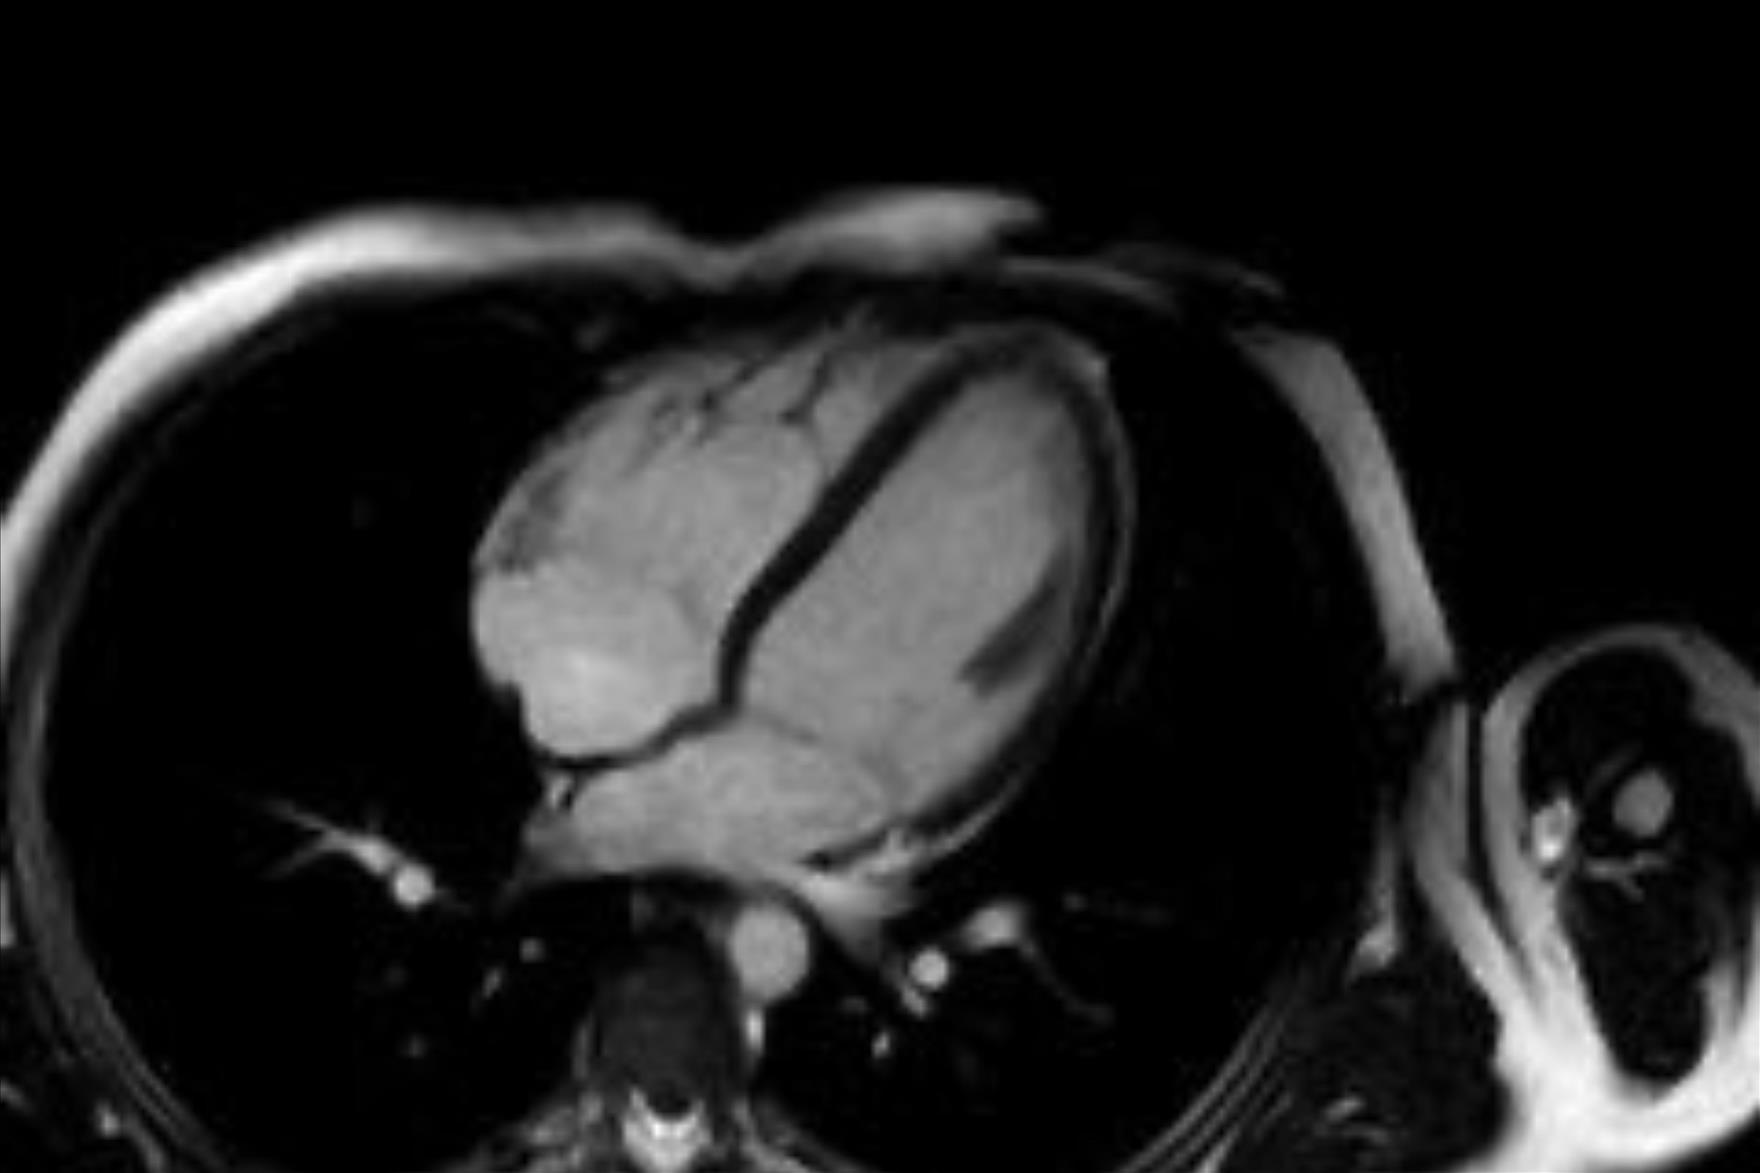

Bu yöntemin hastada kalp hastalığı, damar tıkanıklığı, akciğer hastalığı veya kanser gibi önemli durumların varlığını veya yokluğunu göstermesi açısından büyük fayda sağladığına değinen Doç. Dr. Vefa Çakmak sözlerine şöyle devam etti: “Özellikle sigara kullanan bireylerde, akciğerin bu durumdan ne derece etkilendiği açıkça görülebiliyor. Böylece, sigara bağımlılarının sıkça sorduğu ‘Acaba kanser miyim?’ sorusuna yanıt bulunmuş oluyor. Uygulamanın herhangi bir zararı bulunmuyor ve kullanılan teknoloji uluslararası standartlara uygun şekilde çalışıyor. Kalp hastalıklarının tanısında bir diğer önemli yöntem olan Kardiyak MR ise, anjiyografi ile tanı konulamayan durumlarda devreye giriyor. Kalp duvarlarının yapısal hastalıkları, kalp kapakçıklarıyla ilgili problemler, demir birikimi gibi daha özel durumların tanı ve takibi için tercih ediliyor. Bu yöntemde radyasyon bulunmuyor. Yaklaşık 25–30 dakika süren bu görüntüleme sırasında hastanın üzerindeki metal eşyalar çıkarılıyor, monitörize ediliyor ve nefes tutma komutlarına uyumu sağlanıyor. Çekim, ilgili hekim istemi doğrultusunda gerçekleştiriliyor ve sonuçlar genellikle bir iş günü içinde hastaya ulaştırılıyor. Hem BT hem de Kardiyak MR görüntülemeleri, uzman ekipler tarafından gerçekleştiriliyor ve elde edilen veriler, tanı sürecinde oldukça değerli bilgiler sunuyor. Bu teknolojiler sayesinde, birçok hastalık erken dönemde saptanabiliyor; gereksiz girişimlerin önüne geçiliyor ve hasta güvenliği en üst düzeyde tutuluyor.”